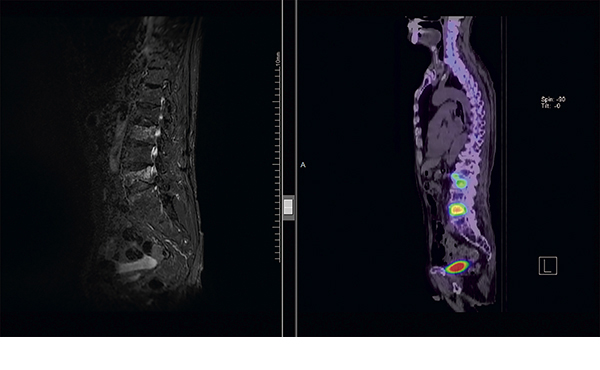

具体的な症例を提示します。症例は90歳前立腺癌の男性。2022年9月に他院泌尿器科で前立腺癌と診断されてホルモン療法のみで加療されてきました。2025年3月に骨シンチにて第2腰椎及び第4腰椎に異常集積を認め、骨転移が疑われましたが、その時は特に症状なく経過観察となりました。4月中旬に腰痛を自覚したため、経緯から骨転移による疼痛増悪と考えられ、緩和照射目的のため当科紹介受診となりました。放射線治療の概要及び予想される主な副作用について説明の上、同意されましたので照射準備の上、2025年5月2日に第2~4腰椎にかけて1回の照射を施行しました。照射終了後、徐々に疼痛が改善、その後は紹介元病院泌尿器科にて経過観察となりました。

※8Gy/1frの照射をL2-L4にかけて照射しました。